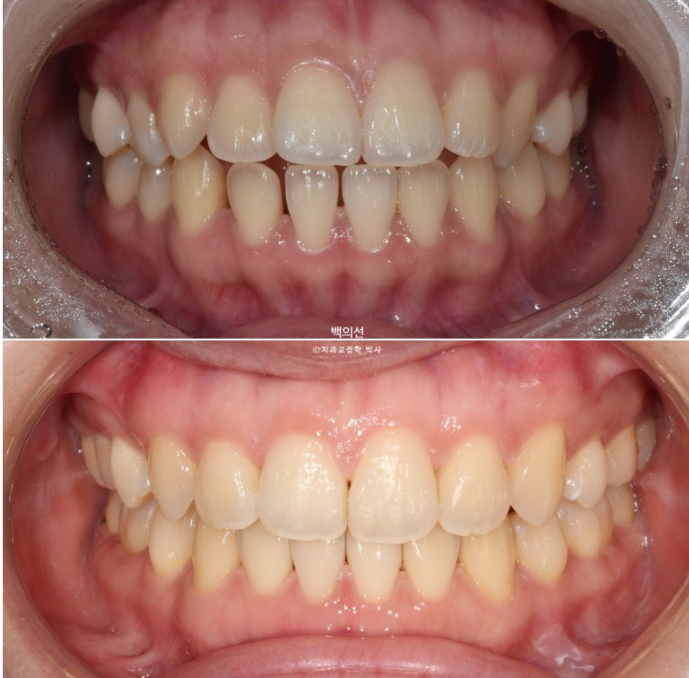

이제 전 후 비교해보겠습니다.

23.01~25.07

맞아진 중심선과 개선된 앞니 개방교합. 이제 면 편하게 끊어 드실 수 있겠어요.

어금니 교합이 기존 3급에서 정1급 교합관계로 바뀌었습니다.

뻗쳐있던 위 앞니가 해소가 되면서 돌출이 해소되었습니다.